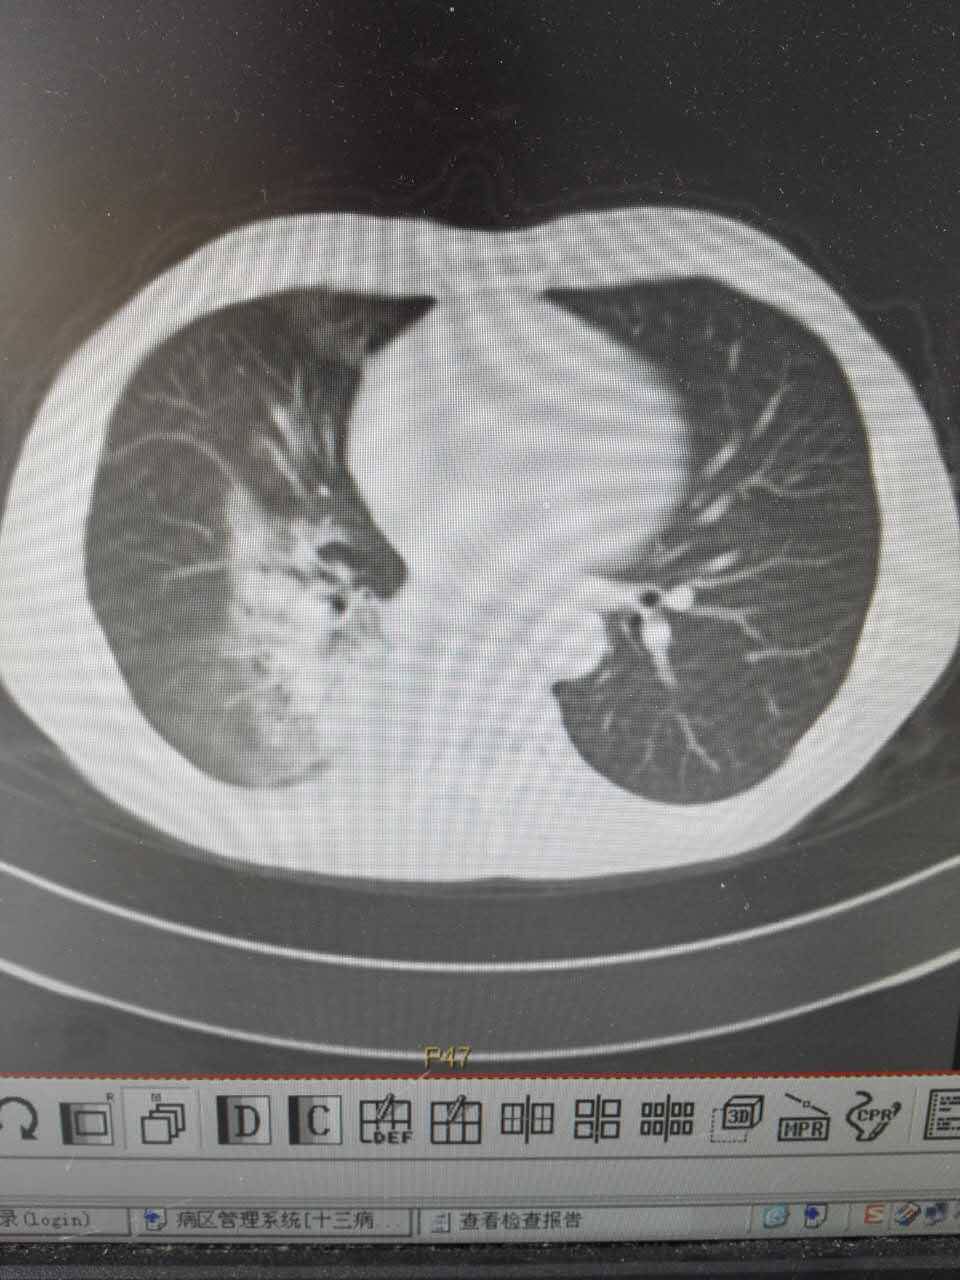

父亲增强CT报告出来了,医生说不是很好(吃克唑替尼才两个多月)

肺部一片一片白色信号,医生说已经看不出来原病灶大小了,说是阻塞性肺炎,该怎么治疗?

颈部淋巴结和肝转症状消失了